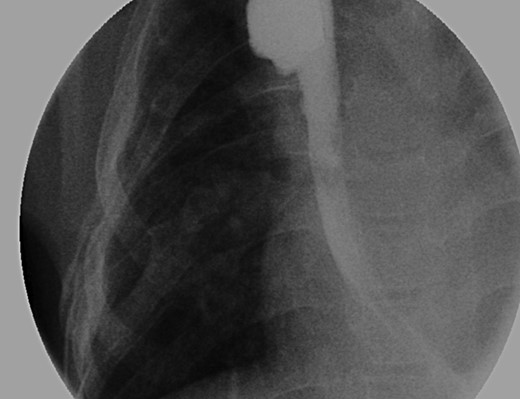

(A) Lateral view during her initial fluoroscopic examination illustrating a small, distal (lower) esophageal remnant present in situ (Black arrows). Contrast was injected through her existing gastrostomy tube. (B) Anterior–posterior (AP) view during initial fluoroscopic examination illustrating an aperistaltic, native colonic interposition in situ with significant dilatation.